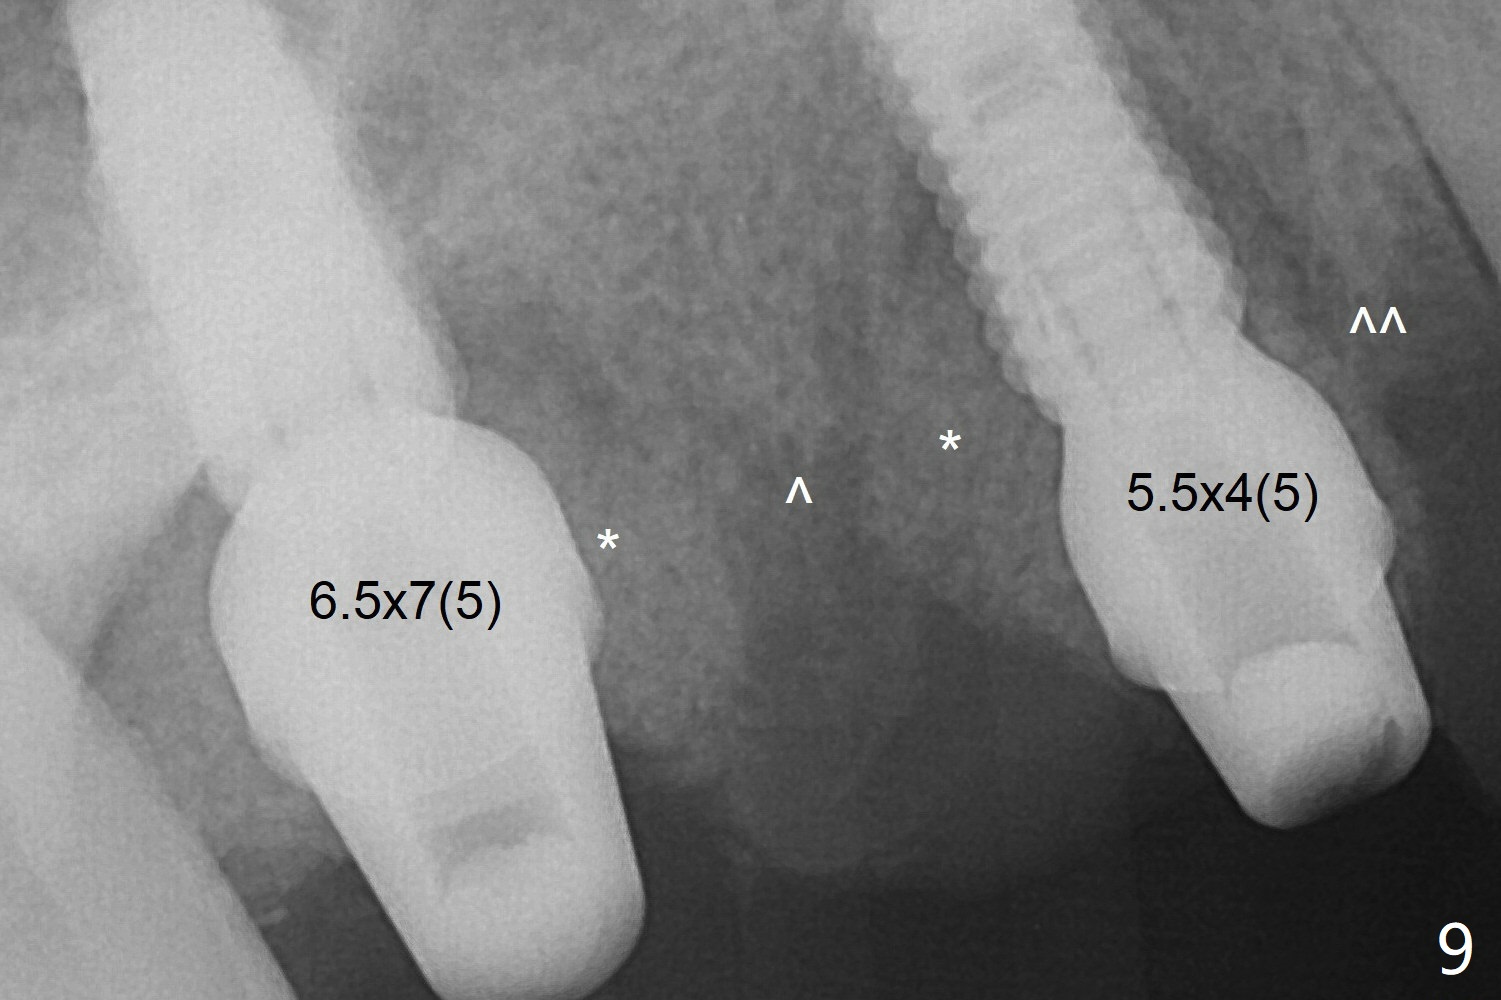

The implant at #5 is seated ~1 mm deeper (subcrestal mesially (^^); supracrestal distally (^)); allograft is placed around the implants prior to insertion of 6.5x7(5) and 5.5x4(5) mm abutments; last more allograft is added (Fig.9 *, 10). There is a large space buccally at #3 and 5, since the implants are placed palatally. Osteogen plug is placed buccally prior to placement of bone graft around the implants. The implants seem to have been osteointegrated 4.5 months postop (Fig.12). The gingiva is healthy around the implants without bone loss 3 months post cementation (Fig.13,14).